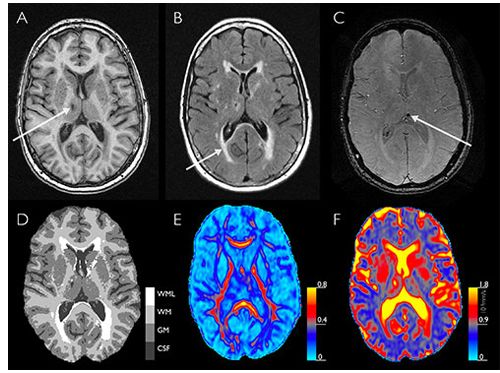

Using diffusion-tensor imaging, researchers found brain changes among patients with mild traumatic brain injury who are depressed or anxious.